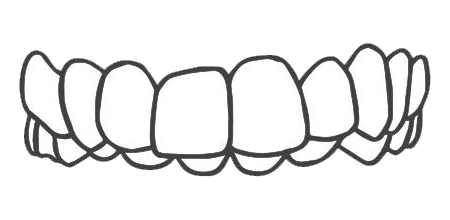

牙列间隙过大

深覆盖

牙列拥挤

深覆颌

开颌

前牙反颌